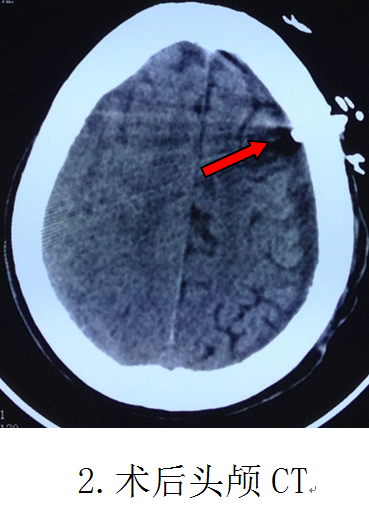

第二天即实施手术,在局部麻醉清醒状态下,顺利实施了微创手术“双管硬通道微创钻孔冲洗引流术”,头皮只有两个0.3厘米直径的点状钻孔穿刺损伤,术中冲洗出血肿100多毫升,整个手术时间仅需30分钟。复查CT血肿完全清除,手术成功。当天晚上病人精神明显好转,偏瘫的右手即能抬起来跟医生握手。第5天下床行走,偏瘫肢体完全康复,取得立竿见影的效果。第8天顺利出院。